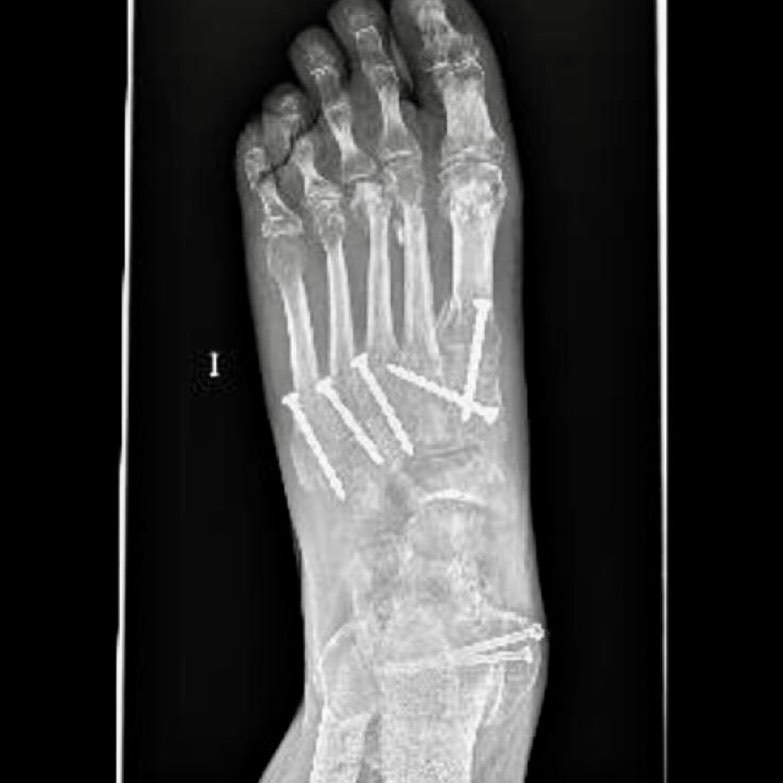

En la rehabilitación postoperatoria nos centraremos no sólo en recuperar la musculatura y movilidad perdidas, si no en elastificar los tejidos retraídos y flexibilizar la posible cicatriz tras la cirugía, reestableciendo poco a poco la funcionalidad del paciente.